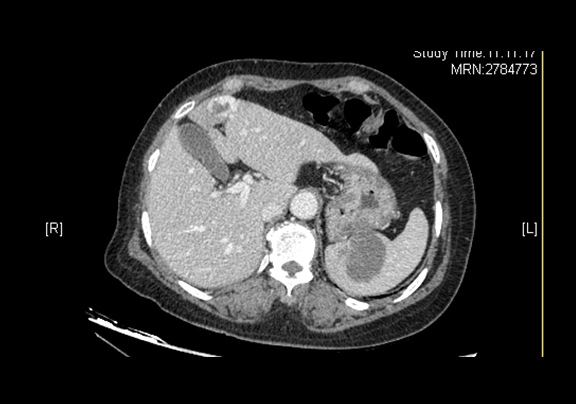

术前CT检查:

动脉期

辅助检查:2015-12-07

全腹CT 肝左叶内略低密度灶,脾脏内略低密度灶

肝胆胰脾彩色多普勒超声检查 脾脏实性占位

上腹部CT平扫 “脾脏术后”改变,请结合临床综合评价,肝脏血管瘤可能性大,请综合临床及其它检查进一步诊断